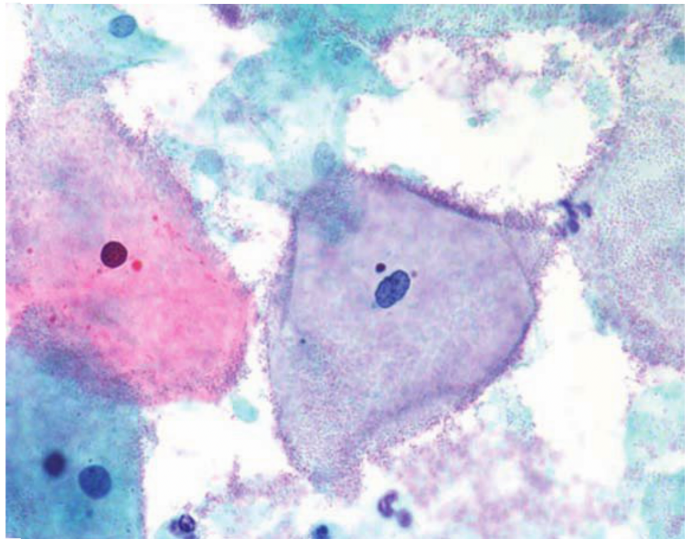

滴虫性阴道炎

报告怎么看?

医生会看到一种带小尾巴(鞭毛) 的灰色小虫。

图片来源于自病理规培笔记